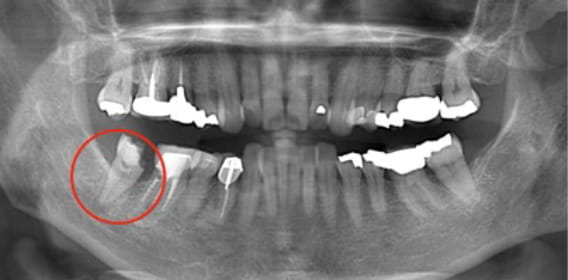

近所のかかりつけの歯科医院で、「再治療できないから奥歯を抜くしかない」と言われた。

あきらめきれず、HPで探して当院へ来院。

外すと中がドロドロに虫歯に感染していました。

折れて残っていた機具を除去

根管の中を洗浄し、無菌に近い空の状態にした。

根管の中を封鎖し終了。

治療後病気がなくなり骨が再生した